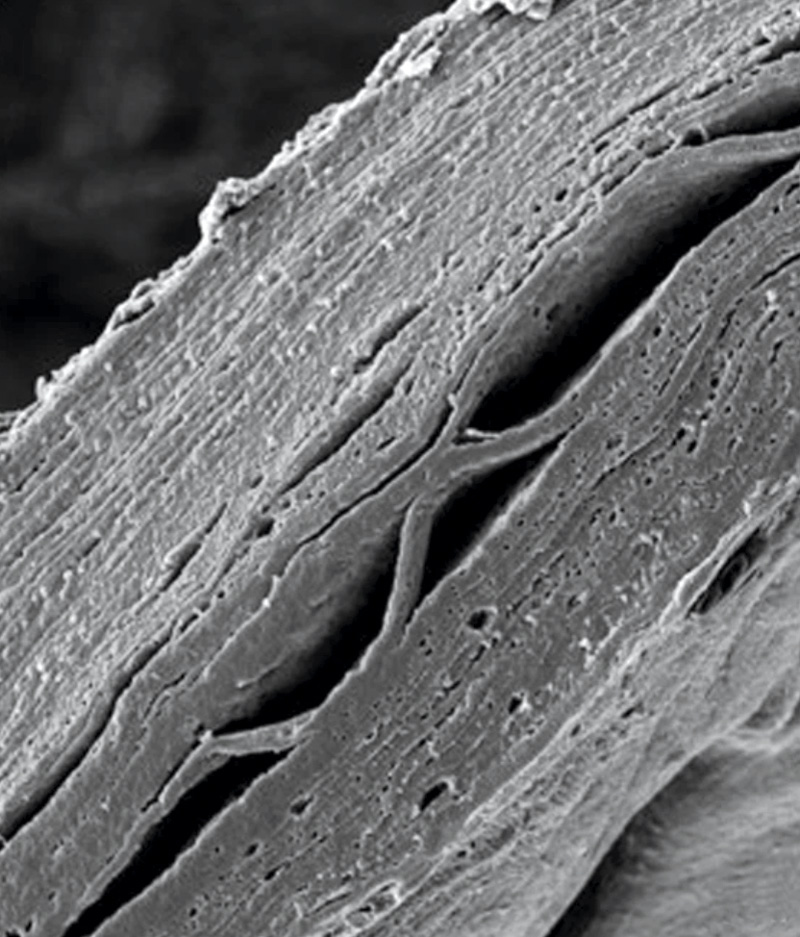

Avelino, T. M. et al. Communications Biology, 2024Epidermis: la bioimpresión en laboratorio consiguió generar capas funcionalesAvelino, T. M. et al. Communications Biology, 2024

En otro paso más en pos de la sustitución de los animales en las pruebas de laboratorio de cosméticos y medicamentos, científicos brasileños del Laboratorio Nacional de Biociencias (LNBio) del Centro Nacional de Investigaciones en Energía y Materiales (CNPEM) de Campinas, produjeron en laboratorio un análogo completo de la piel humana. La bióloga Ana Carolina Figueira y su equipo utilizaron una combinación de tres tipos de células humanas (queratinocitos, fibroblastos y células madre mesenquimales). El proceso de impresión se llevó a cabo utilizando biotinta de colágeno, cuya consistencia es líquida a 4 grados Celsius (ºC) y que, tras incubársela a 37 ºC, adquiere la consistencia del tejido epitelial. Una vez impresas, las capas de piel se diferenciaron, constituyendo la epidermis, con su superficie impermeable, y la dermis. Las células madre se transformaron en adiposas, formando la hipodermis. Esta capa reveló que interviene en la activación de genes específicos para el mantenimiento de la fisiología de la piel, la proliferación y la diferenciación celular y en la hidratación de la piel (Communications Biology, 11 de noviembre).